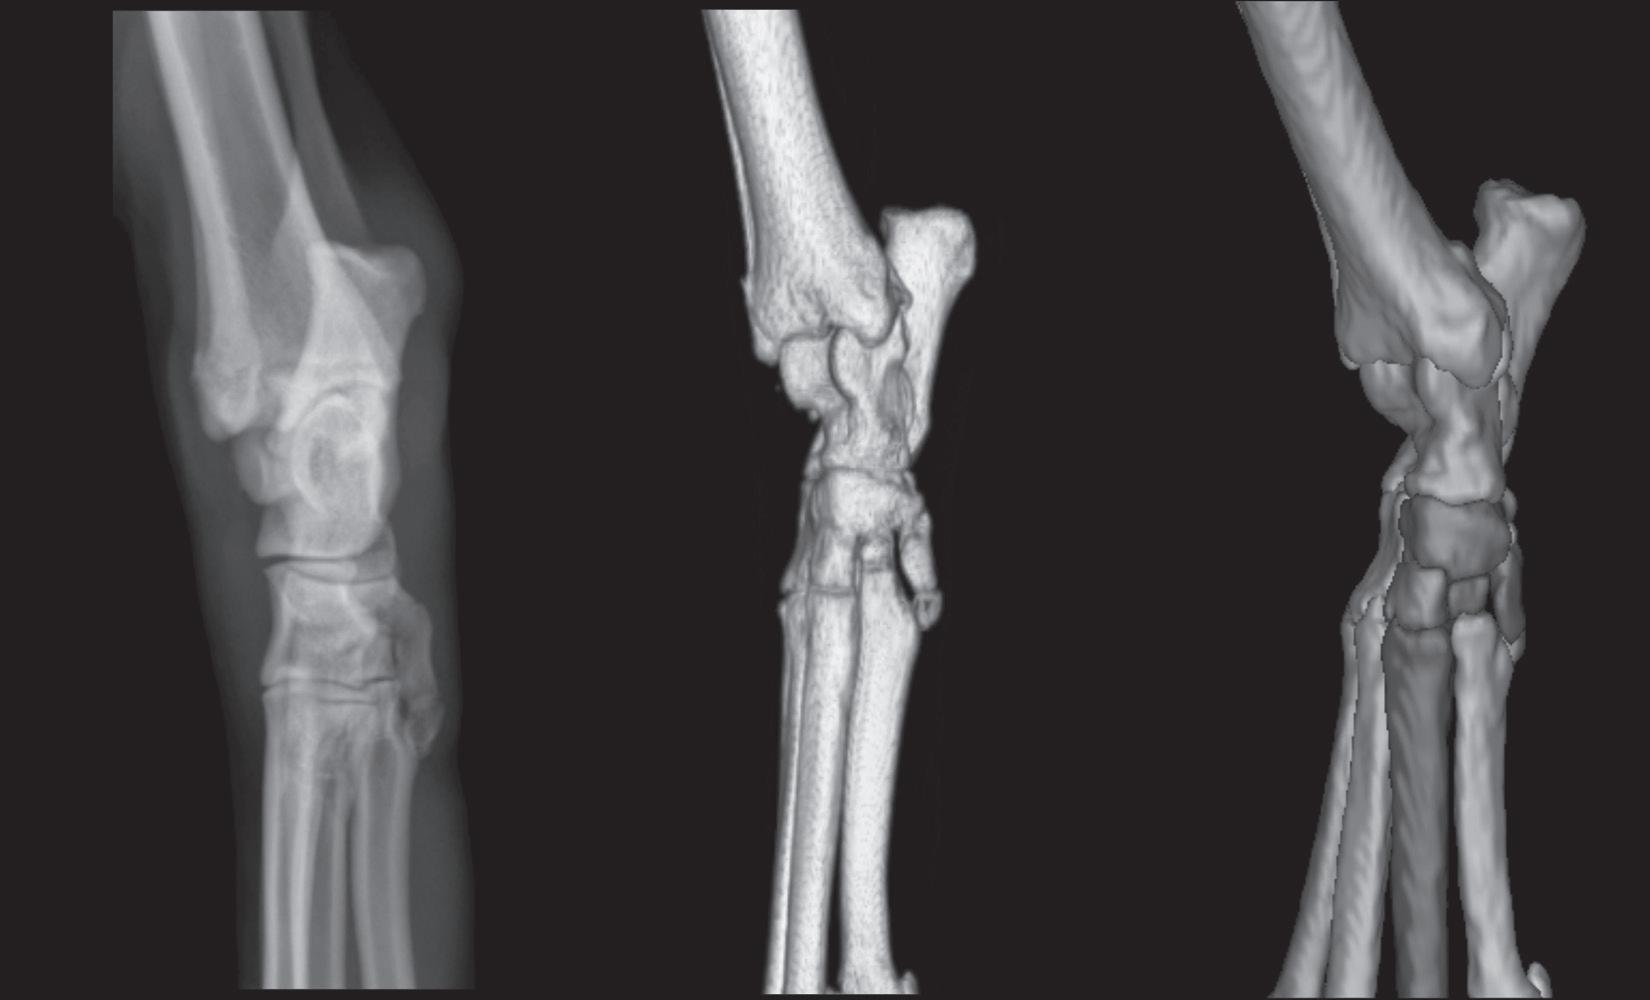

Figure 1-12. The left panel is a dorsal 45-degree medial-plantarolateral radiograph of a canine tarsus. The middle panel is a three-dimensional rendering of a normal right canine tarsus as seen from the perspective of the x-ray beam when making a dorsal 45-degree medialplantarolateral radiograph. The right panel is identical to the middle panel, but where each bone has been colorized (see Color Plate 3). Colorizing makes it easier to comprehend the extent of overlap. Note in the radiograph that the only edges that can be evaluated are the dorsolateral and plantaromedial edges. Even though the proximal aspect of the calcaneus is plantarolateral, it can still be seen in this view because it extends suffciently proximal that it will not be superimposed on the tibia.